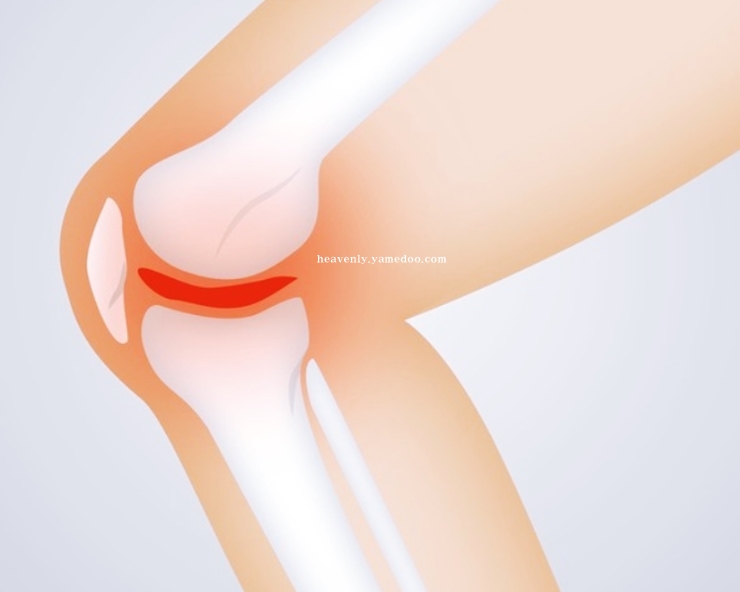

반월상 연골판이란, 무릎 관절 사이사이에 있는 반달 모양의 물렁뼈입니다. 우리의 체중을 견디는 작용을 하는 부위입니다. 무릎 안쪽과 바같쪽에 양쪽에 하나씩 있습니다. 뼈와 뼈가 부딪힐 때 손상되지 않도록 하거나 완충효과를 가지고 오는 것이 바로 반월상 연골판입니다.

무릎에서 쿠션 역할을 하는 반월상 연골판이 파열되면 뚝뚝하고 무릎에서 소리가 나게됩니다. 또 무릎이 삐걱대거나 뻑뻑한 느낌이 듭니다. 반월상 연골판에 문제가 발생하면 조금만 걸어도 통증이 나타나고 경사로 또는 계단을 오를 때 갑자기 다리에 힘이 풀려 주저앉는 일이 발생할 수 있습니다.

무릎통증 원인 이는 반원상 연골판 파열을 의심해볼 필요가 있겠습니다.

만약 연골판 손상을 방치하면 퇴행성 관절염으로 발전할 수 있습니다. 반월상 연골판이 제 역할을 하지못해 각종 부위에 손상이 발생되면 무릎에 있는 관절을 보호하는 기능을 하지 못해 무릎을 구부리거나 움직일 때 심한 통증을 초래하기 때문입니다. 반월상 연골판의 중요성을 다시 한 번 깨닫게 되었습니다.

무릎통증 원인 초기에는 단순한 타박상으로 오인할 수 있습니다. 그런데 치료하지 않고 방치하면 뼈와 뼈가 서로 맞닿으며 퇴행성 관절염을 불러옵니다. 반월상 연골판은 혈관이 존재하지 않아 한 번 손상되면 자연적인 치유 또는 재생이 어렵운 신체부위입니다.